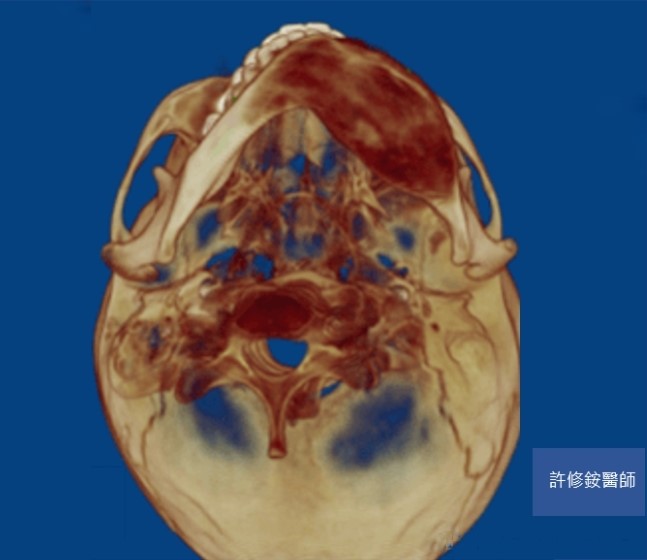

削骨手術需要精密的診斷與計算,加上顏面骨骼有特殊的圓弧與角度,精確的影像是基本要求。3D影像可協助醫師能檢視不同的切面,且影像重組後,專科醫師可自由旋轉影像由各種不同的角度檢視骨骼的變異,除了能完整地檢視病人的顏面骨並精準的訂定治療計劃;客人也能在手術前,藉由3D影像的模擬更理解醫師的解釋內容。

正顎、削骨手術需要精密的診斷與計算,加上顏面骨骼有特殊的圓弧與角度,精確的影像是基本要求。感謝科技進步,3D影像使醫師能檢視不同的切面,且影像重組後,醫師可自由旋轉影像由各種不同的角度檢視骨骼的變異。因此,醫師能完整地檢視病人的顏面骨並精準的訂定治療計劃。病人也能藉由3D影像的模擬更理解醫師的解釋內容。

(黃)過度發育之下顎骨角 (黑線)過度平緩下顎下緣

(紅)下顎骨理想角度120度 (黃)下顎平面角想角度30度

骨頭的切除量依據每個人的需求而有不同。但原則是重新塑造理想的下顎骨角角度以符合美觀(約呈120度),且重新建立下顎平面角(約呈30度),改善下臉部過短的視覺效果。